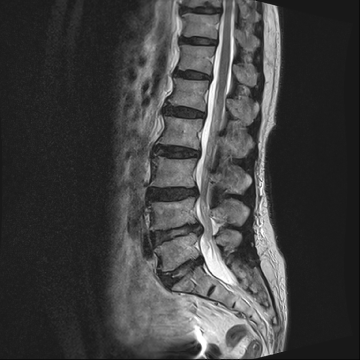

요추 협착증 수술 전·후

2020.08.30

2022.09.06

ㆍ환자 동의를 받은 자료이며, 이미지 사진은 실물과 다를 수 있습니다.

ㆍ모든 자료는 새움병원 자료입니다.